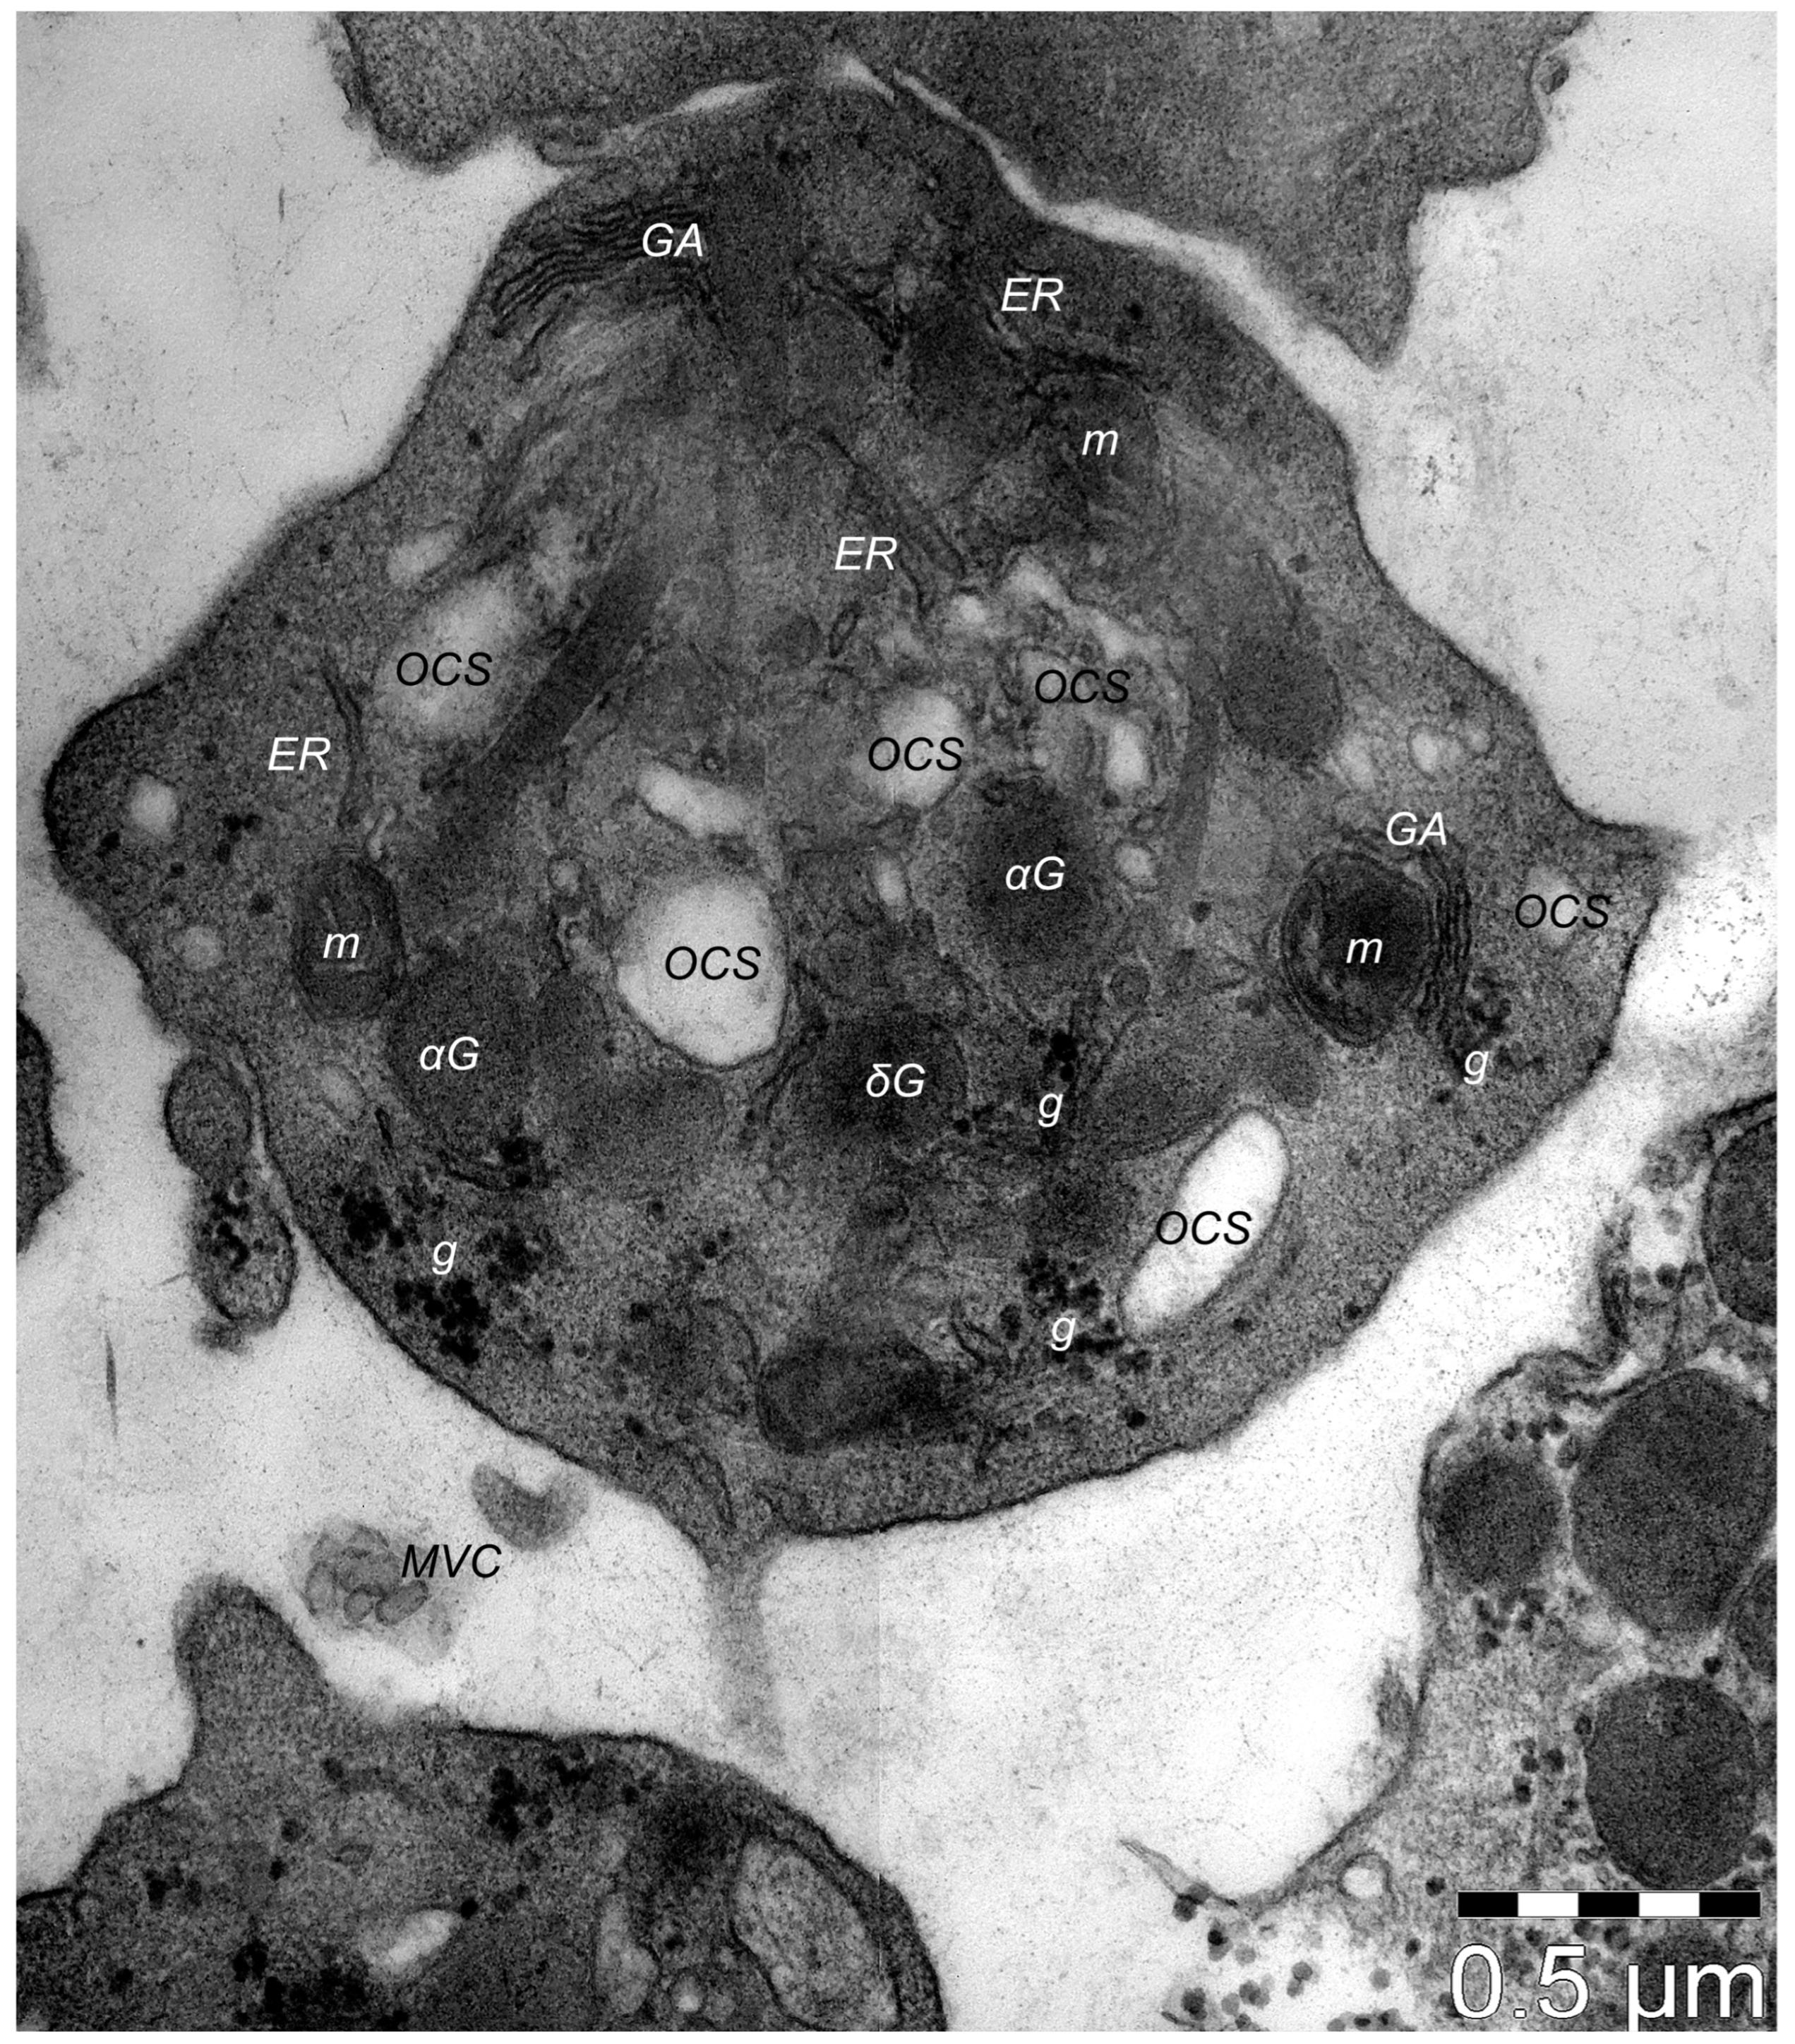

9. Dermal TCs: A Distinct Cell Population with a Promising Skin Regenerative Potential

- Rusu, M.C.; Mirancea, N.; Mănoiu, V.S.; Vâlcu, M.; Nicolescu, M.I.; Păduraru, D. Skin Telocytes. Ann. Anat.—Anat. Anz. 2012, 194, 359–367. [Google Scholar] [CrossRef] [PubMed]

- Manole, C.G.; Soare, C.; Ceafalan, L.C.; Voiculescu, V.M. Platelet-Rich Plasma in Dermatology: New Insights on the Cellular Mechanism of Skin Repair and Regeneration. Life 2023, 14, 40. [Google Scholar] [CrossRef] [PubMed]

- Wang, L.; Xiao, L.; Zhang, R.; Jin, H.; Shi, H. Ultrastructural and Immunohistochemical Characteristics of Telocytes in Human Scalp Tissue. Sci. Rep. 2020, 10, 1693. [Google Scholar] [CrossRef] [PubMed]

- Mirancea, N.; Moroşanu, A.-M.; Mirancea, G.-V.; Juravle, F.D.; Mănoiu, V.S. Infrastructure of the Telocytes from Tumor Stroma in the Skin Basal and Squamous Cell Carcinomas. Rom. J. Morphol. Embryol. 2013, 54, 1025–1037. [Google Scholar] [PubMed]